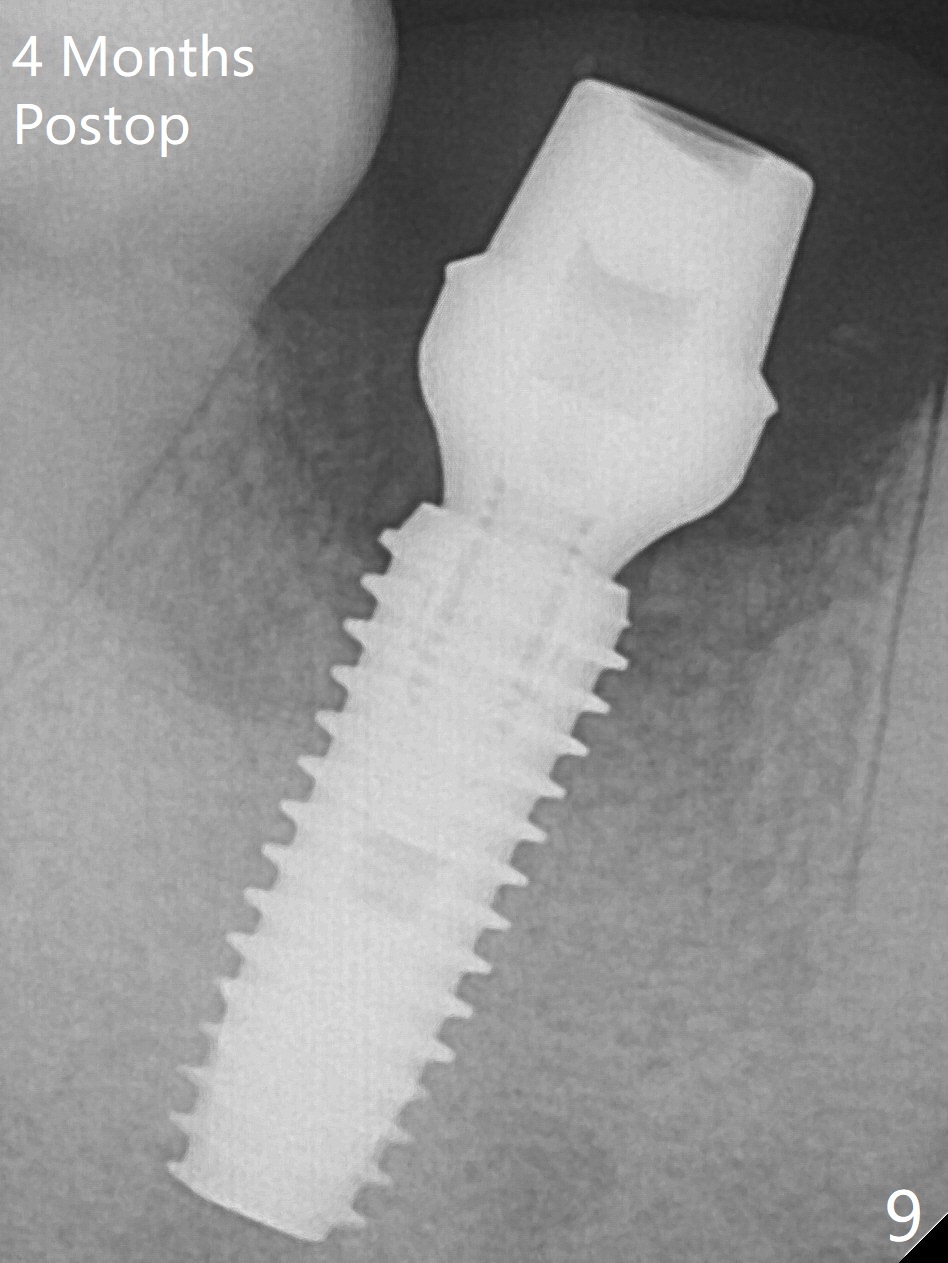

Fortunately no paresthesia is reported postop. Why is the Inferior Alveolar Canal not violated? Fig.7 is a coronal section of CBCT taken for a 40-year-old man at the lower 1st molar (at the septum). At the region, the Canal (brown circle) is close to the lingual plate (L). Because of severe bone loss of the lingual plate of this case (Fig.8 *), osteotomy is intentionally created buccal (green). The deep osteotomy may not contact the Canal, while the hemorrhage may stem from the medullary space (M in Fig.4,7). Bone morphology at the coronal end of the implant apparently changes 4 months postop, suggesting osteointegration (Fig.9). Impression is taken. Bone density around the implant at the crest seems to increase (Fig.10), while there is no soft tissue deficiency 10 months post cementation (Fig.11). The bone appears to regenerate toward the abutment, particularly distally, 14.5 months post cementation (Fig.12). Periimplantitis develops (bleeding on water pik and erythematous and tender buccal gingiva) 1 year 7 months post cementation (Fig.13,14). The 1st three threads are exposed (*). Bone graft with PRF and 6-month membrane or Cytoplast will be needed. Pain disappears 3 days of oral antibiotic. The gingiva looks healthy 1 month later when he returns for bone graft (Fig.15). But the lingual gingival cuff is not so healthy when the crown/abutment is removed (Fig.16 <). Bone graft is not done. For those patients with suboptimal oral hygiene, implants should be placed as low as possible, better with guide for precision.